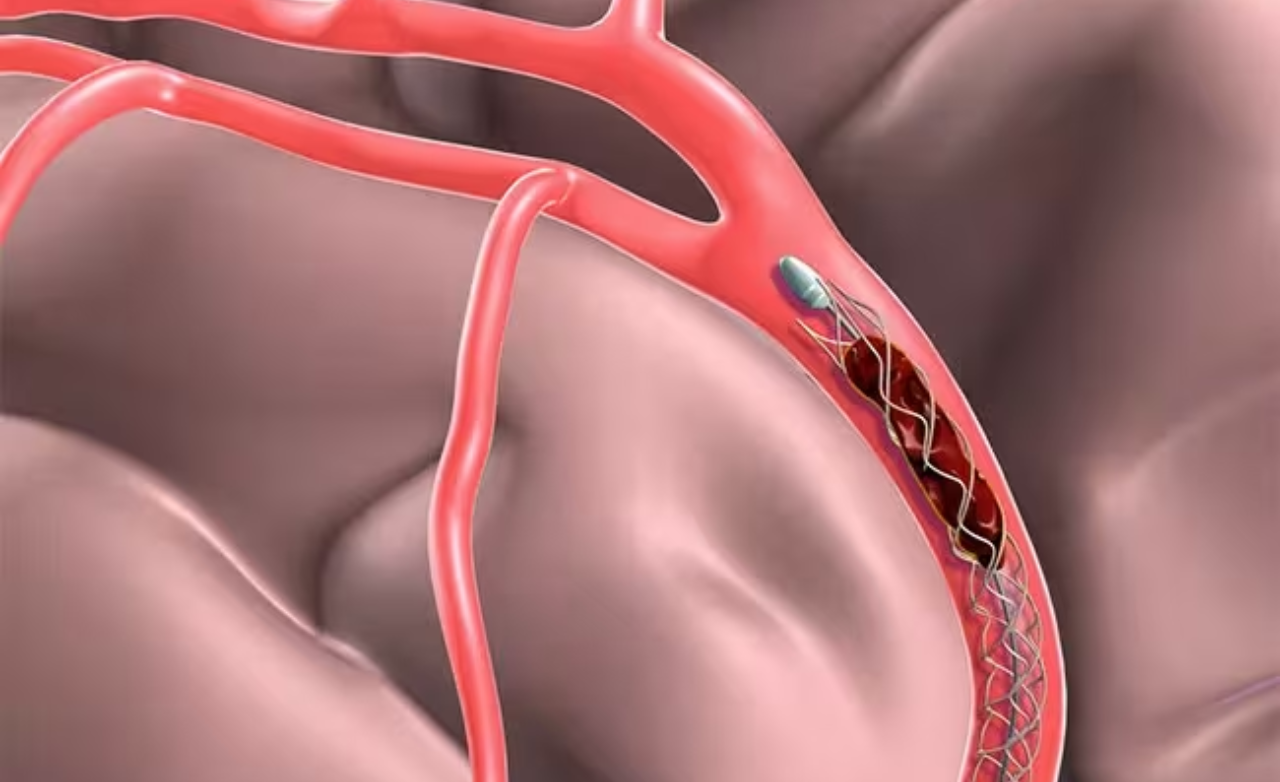

Mechanical thrombectomy is an emergency procedure for strokes caused by blocked brain arteries. It is performed when sudden weakness, speech difficulty, or paralysis occurs.

Special catheters remove the clot quickly, restoring blood flow, minimizing brain damage, and significantly improving recovery when done within the treatment window.